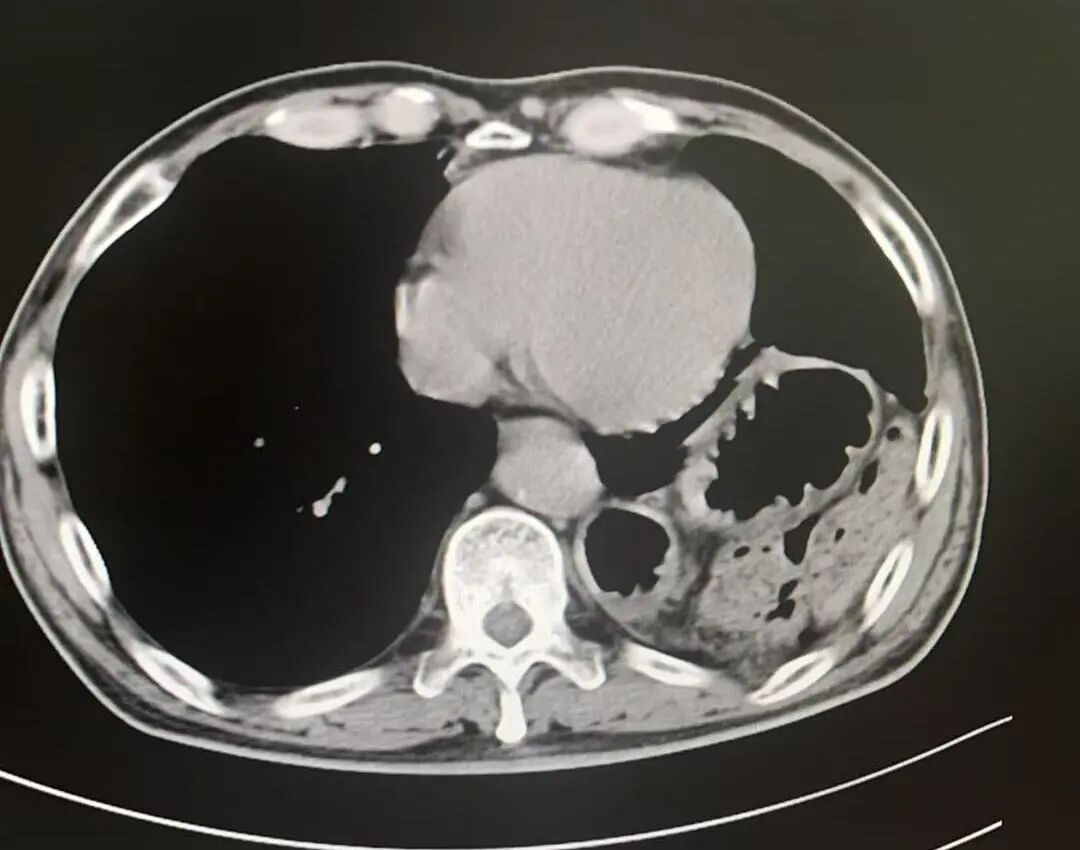

術(shù)后影像

膈疝修補如拆“定時炸彈”,需松解粘連、歸位臟器、修復(fù)缺損三步精準(zhǔn)到位。團(tuán)隊采用階梯策略,在確保手術(shù)效果的同時最大程度降低風(fēng)險、減少創(chuàng)傷。術(shù)后,劉大爺?shù)陌Y狀迅速緩解,現(xiàn)已康復(fù)出院,重歸正常生活。